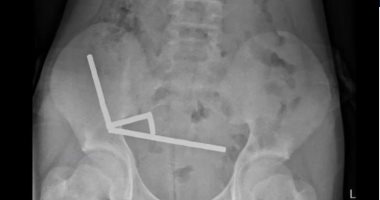

وقال المسؤولون، إن المغناطيسات التي تم حظرها فى نيوزيلندا منذ يناير2013 تم شراؤها من منصة للتسوق عبر الإنترنت تيمو، وأظهرت الأشعة السينية أن المغناطيسات قد تكتلت في أربعة خطوط مستقيمة داخل أمعاء الطفل، وبدا أنها فى أجزاء منفصلة من الأمعاء ملتصقة ببعضها البعض بفعل القوى المغناطيسية.